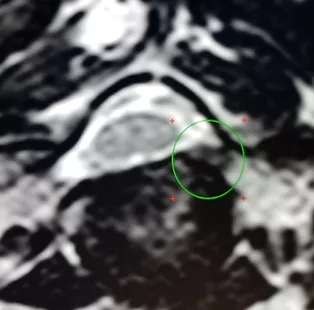

Основным методом диагностики грыж шейного позвоночника является МРТ. Необходимо выполнить МРТ на аппарате с напряжением магнитного поля не ниже 1,5 Тесла и записывать на диск. Ниже представлен аксиальный срез МРТ на уровне грыжи. Показана зеленым кружком фораминальная грыжа межпозвонкового диска, которая сдавливает спинномозговой корешок С7. Грыжа такой, фораминальной локализации является идеальным вариантом для эндоскопической операции при шейной межпозвоночной грыже с помощью полностью эндоскопической задней цервикальной фораминотомии.